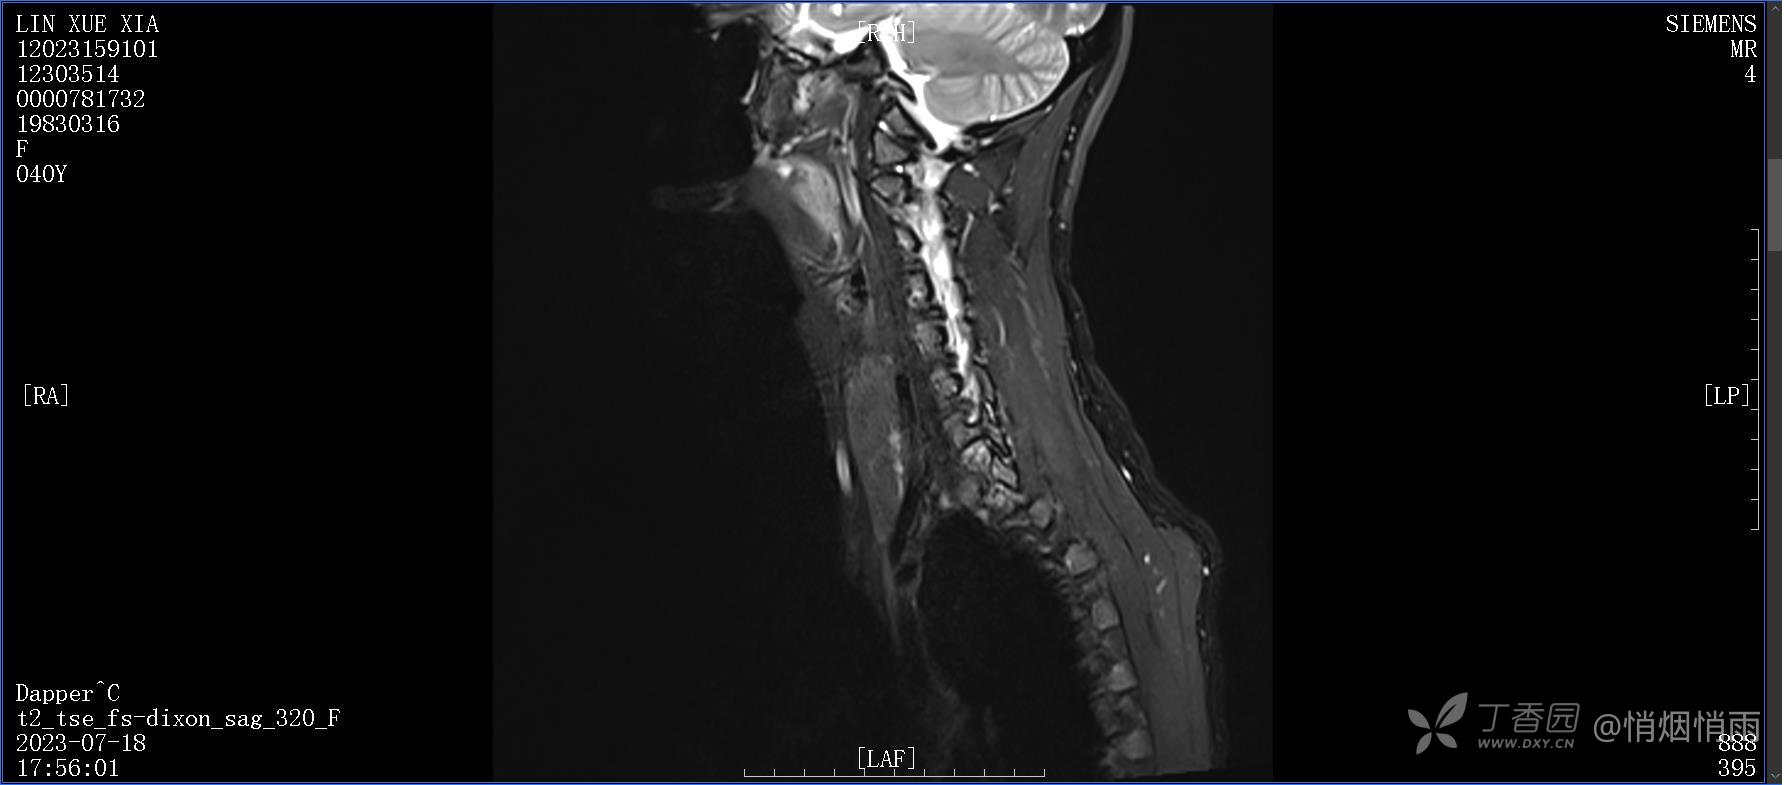

NeurothinkerZ 推荐患者女性,40岁,因右肩背部疼痛班活动受限4日余入院(2023-07-17)。

病史:入院前4天无明显诱因突然感右肩背疼痛伴随活动受限,自行口服依托考昔、艾瑞昔布等药物治疗,院外应用肩关节局部手法按摩等,均无明显改善。外院门诊诊为颈椎病。自诉既往多次“胸椎小关节紊乱”于当地诊所行手法按摩,治疗后好转,否认慢性疾病病史、外伤史、手术史,诉青霉素过敏,无其他药物食物过敏史,否认吸烟史、饮酒史,月经正常,经量正常。

查体:右肩关节局部轻度肿胀,肩胛区压痛明显,痛处不固定,肩关节痛性活动受限,jobe test(+),lift -off test(+),中指、环指感觉较余指减退,余肢端感觉及血运情况可。

目前的诊断,暂时依据辅助检查诊为肩袖损伤,但是患者疼痛的性质和特点,却不是单纯的肩袖损伤所致。考虑过胸廓出口综合征,但是该疾病会出现肩胛区的疼痛吗?(由于考虑到费用的问题,没再进行下一步的检查)带状疱疹会有如此的症状吗?